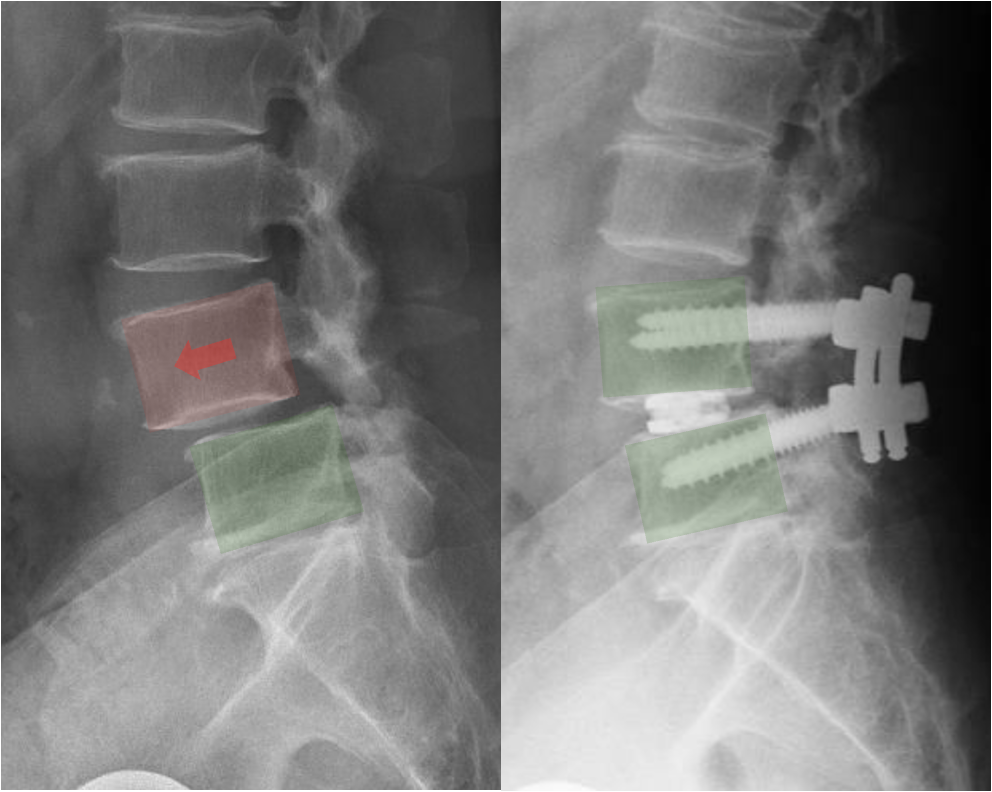

X-ray image showing a spine with spinal fusion hardware and highlighted areas indicating a herniated disc and spinal fusion screws

• Lumbar spondylolisthesis

• Lumbar spinal stenosis with instability

• Lumbar degenerative disc disease

• Recurrent disc herniation

• Severe lower back pain related to disc degeneration

TLIF is often chosen when stabilizing the spine can improve symptoms and prevent further motion between vertebrae.